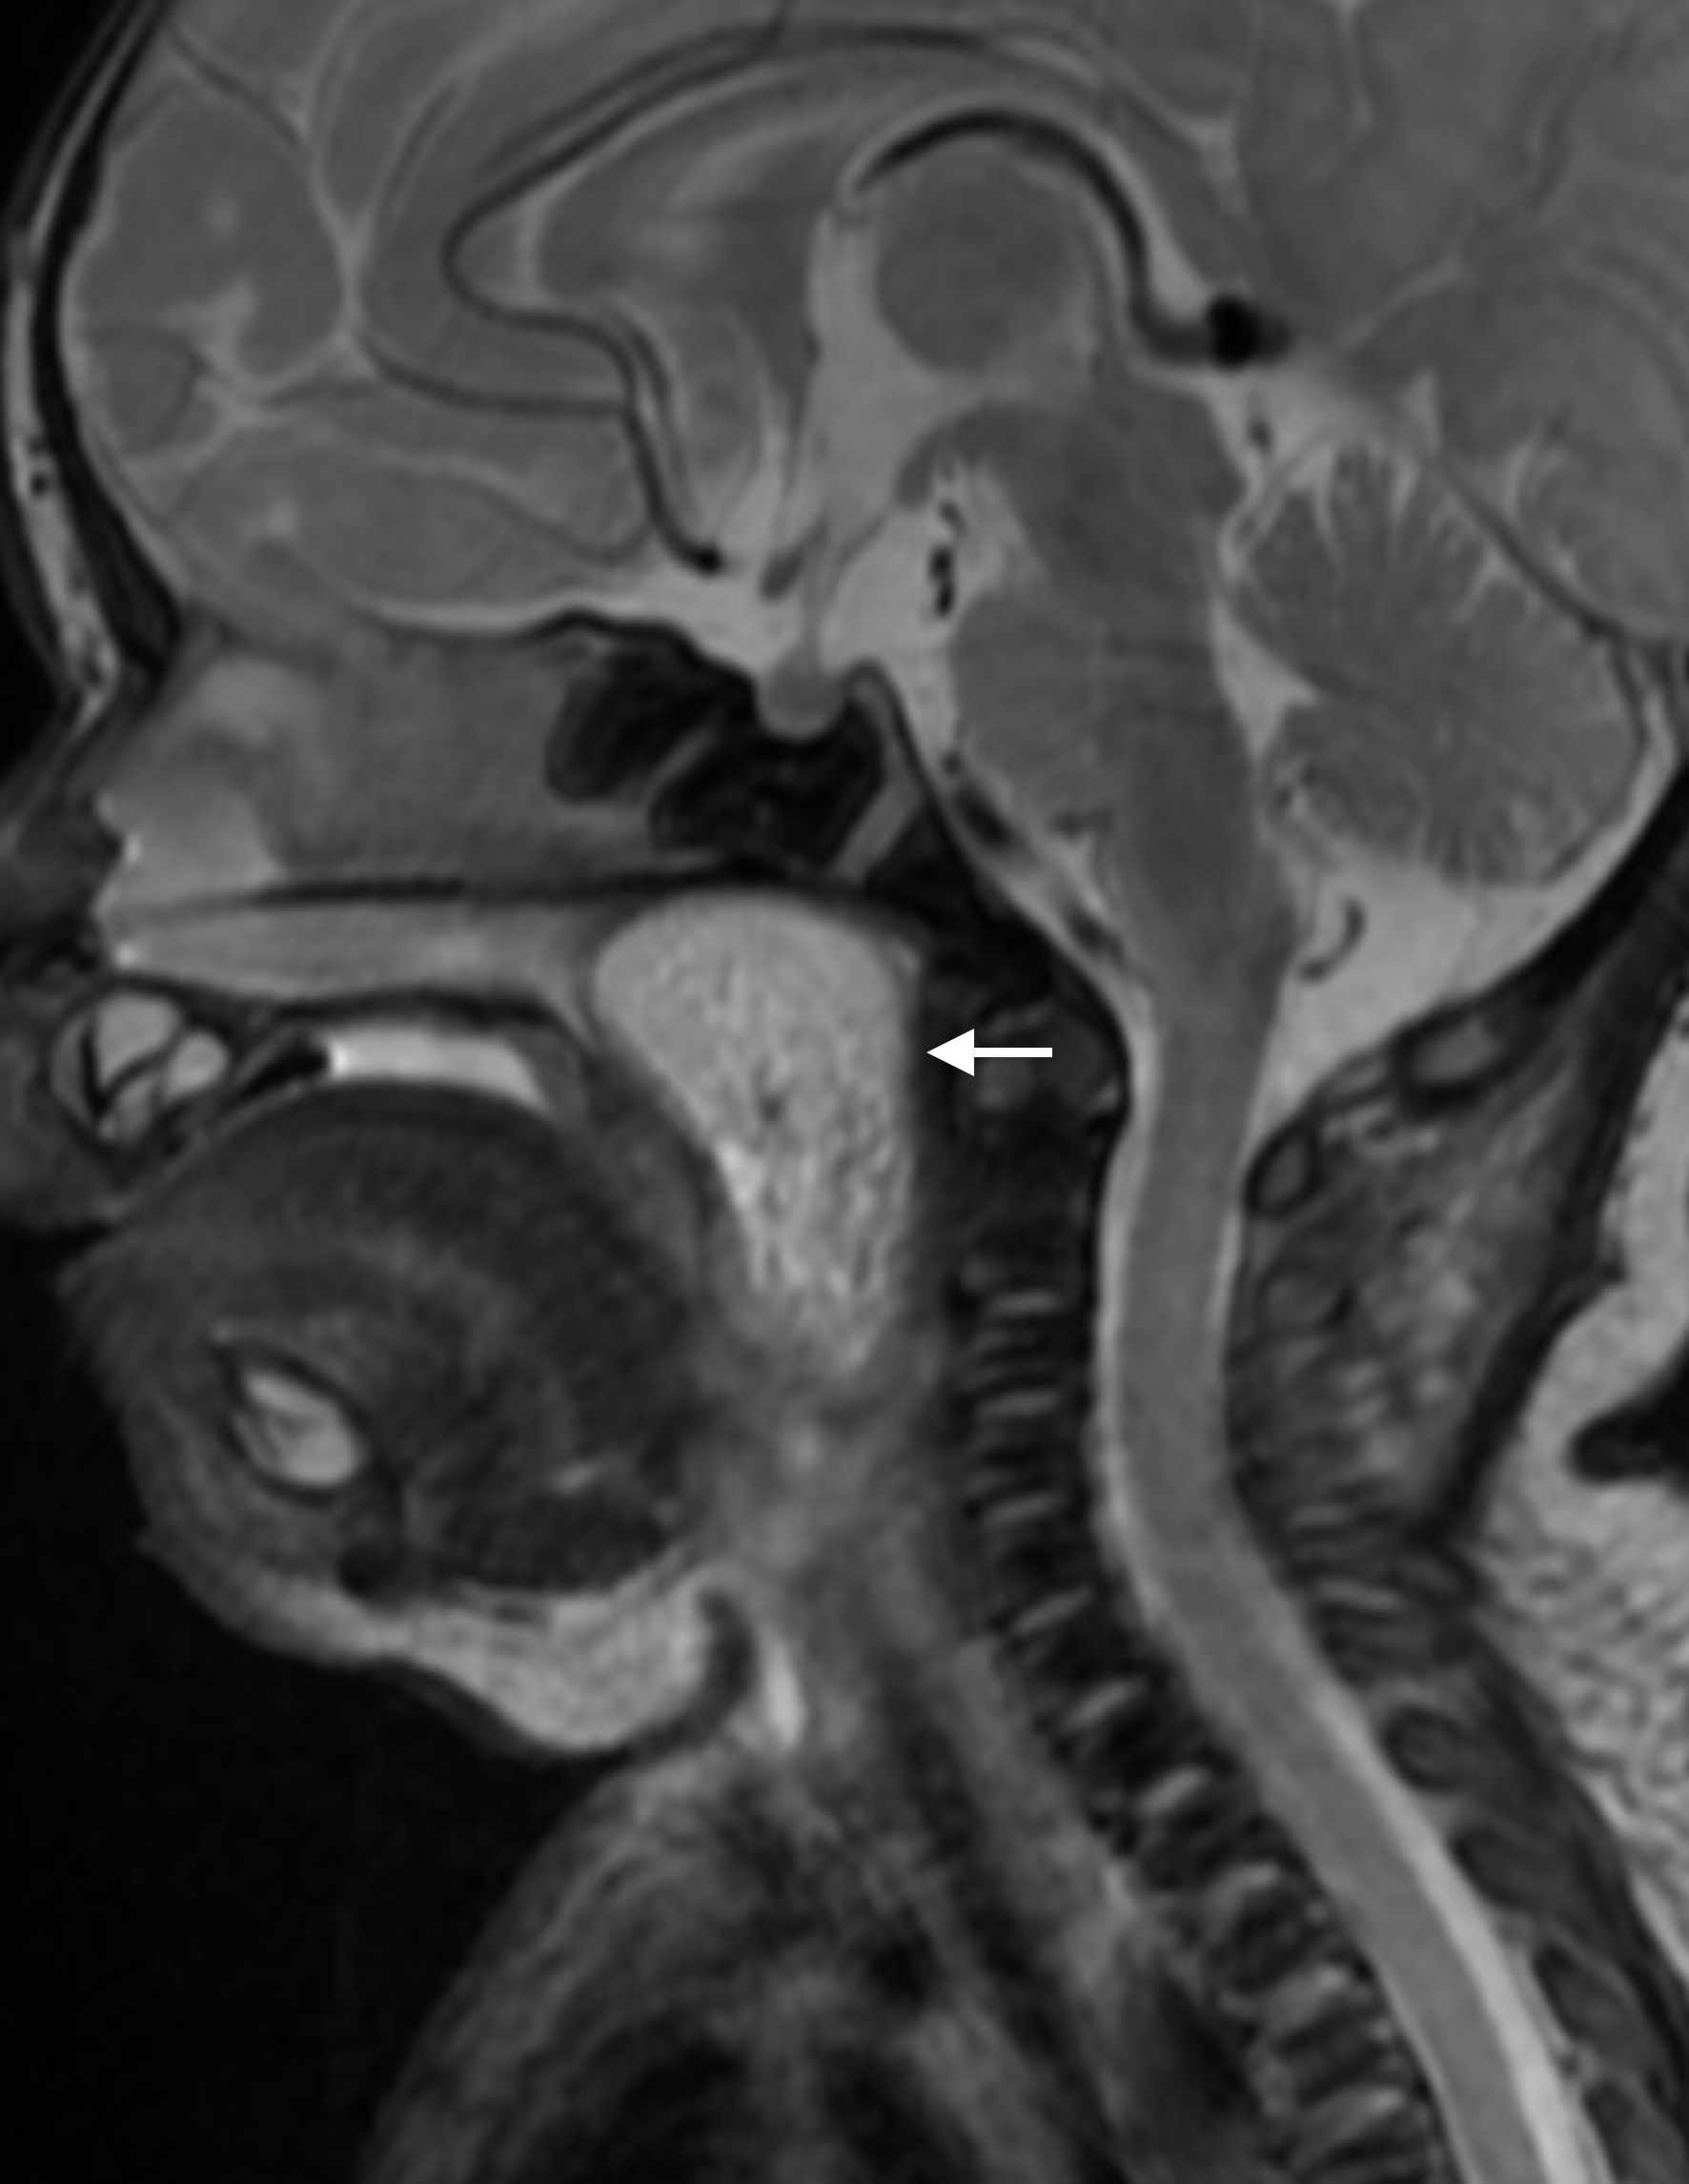

Pharyngeal hairy polyps are rare lesions that arise from the nasopharynx or oropharynx. It occurs predominately in females, with predilection for the left side. Its etiology remains poorly understood. It typically presents in the neonatal period with respiratory distress and feeding difficulties. Imaging is fundamental to identify the high fat content of the lesion. Surgical resection is the treatment of choice. We report a case of a nasopharyngeal hairy polyp causing respiratory distress since birth.